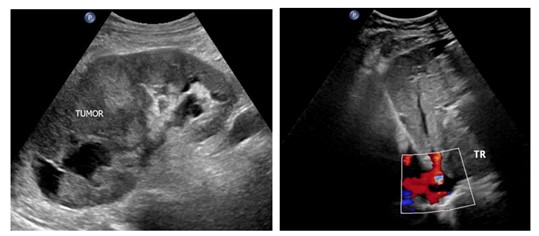

Examination: ultrasound - hypervascular tumor of the right kidney, tumor thrombus in the renal and inferior vena cava (Mayo III) (Fig. 1); MSCT - tumor of the right kidney, tumor thrombus in the inferior vena cava (Fig. 2); coronary angiography - critical stenosis of the coronary arteries (stenosis of the anterior interventricular branch (AIB) in the middle third up to 85-90%) (Fig. 3).

Figure 1: Ultrasound: a – kidney tumor (TUMOR); b - inferior vena cava tumor thrombus (TR)